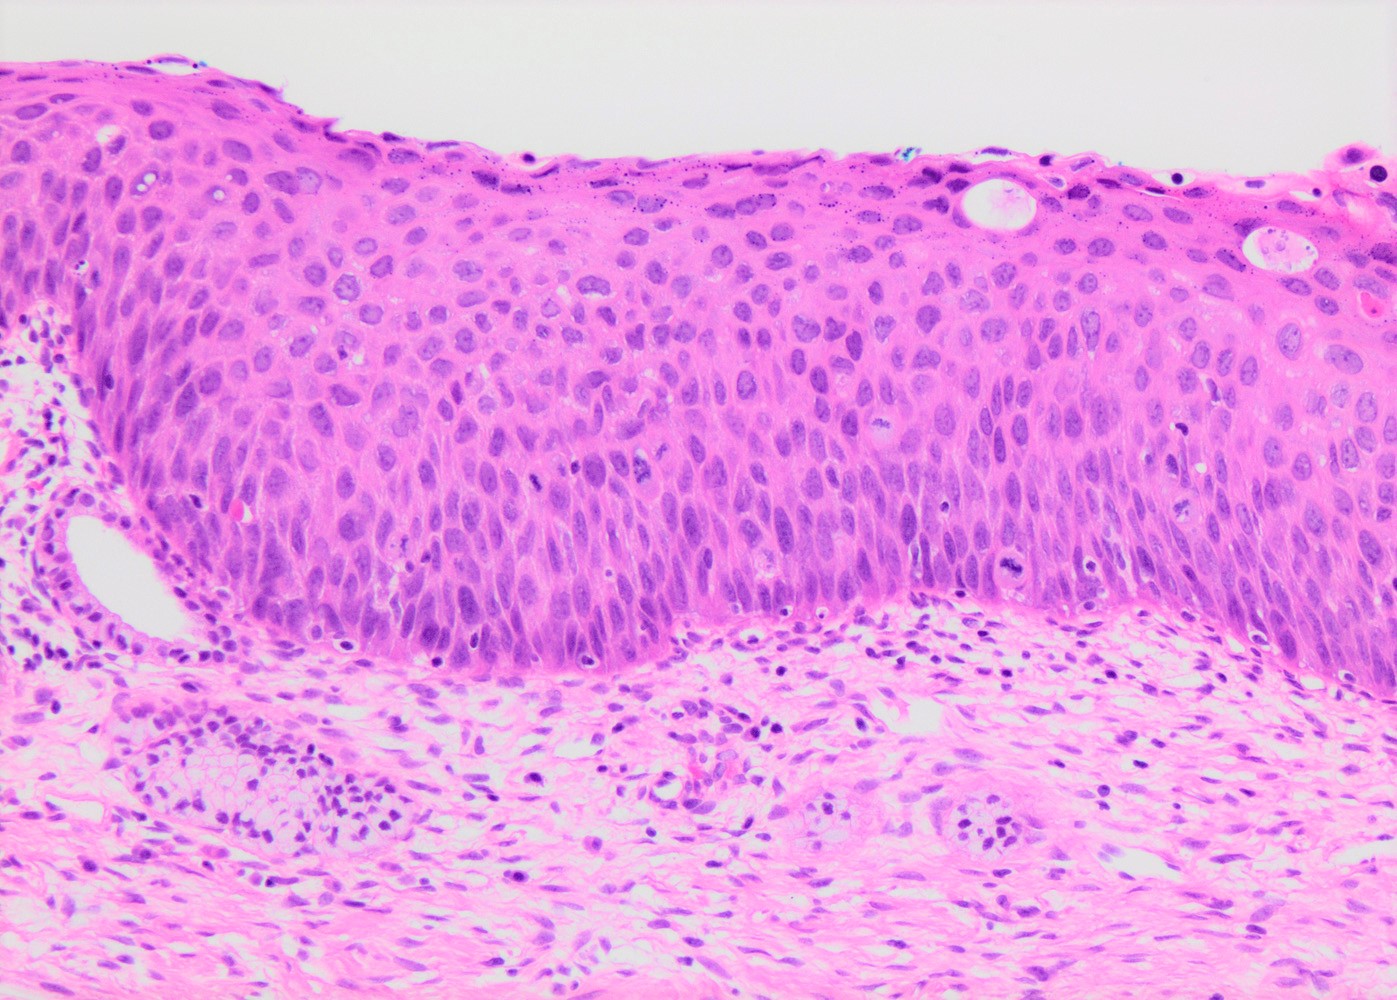

- Conventional / classic pattern: full thickness nuclear abnormalities (hyperchromasia, coarse chromatin, irregular nuclear contours and inconspicuous nucleoli), high N/C ratio in at least lower two - thirds of epithelium

- CIN II: cytoplasmic maturation in the upper third of mucosa

- CIN III: full thickness basal / parabasal type, no maturation difference across layers

- Increased mitotic activity with atypical mitoses

Microscopic (histologic) images

Contributed by Khaled J. Alkhateeb, M.B.B.S.